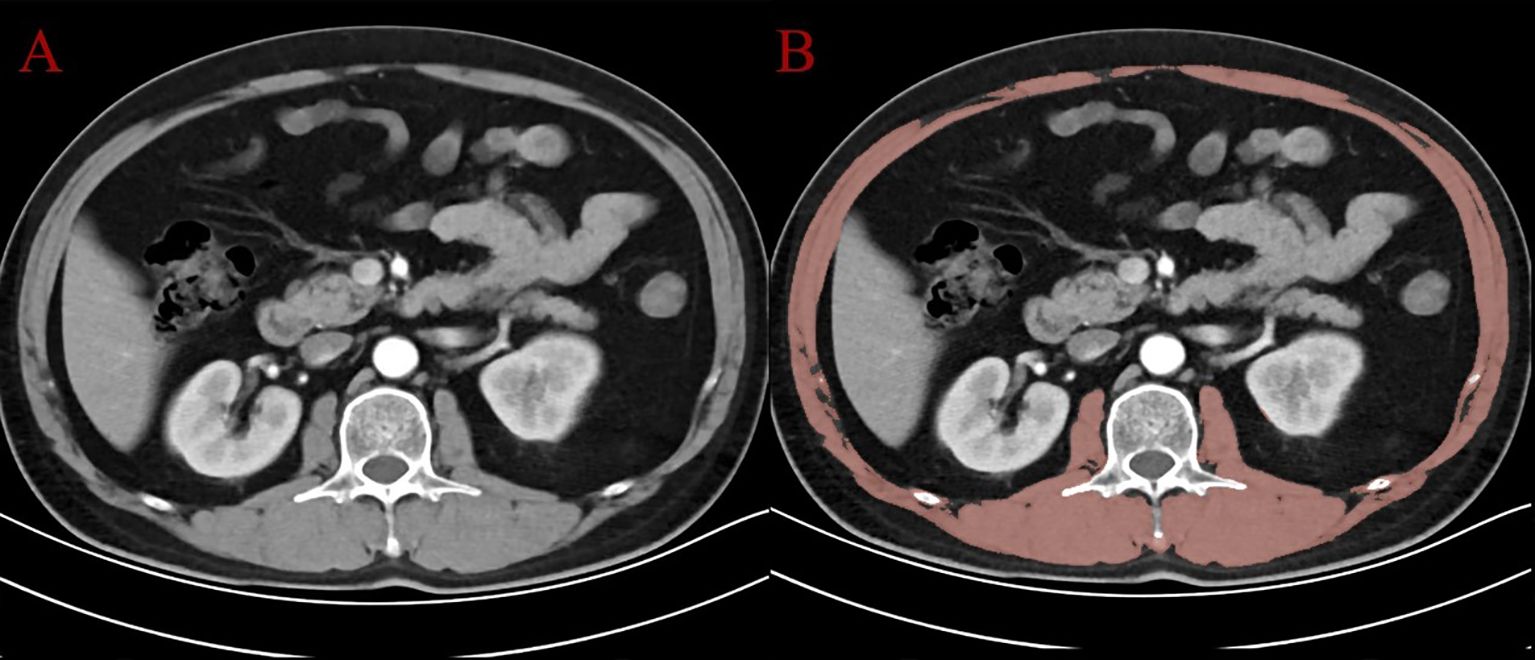

Objective: This study aimed to explore the combined impact of sarcopenia and physical performance on immune status and prognosis in patients with resectable gastric cancer, and to evaluate the mediating role of immune function. Methods: A retrospective cohort of 413 patients undergoing radical gastrectomy was analyzed. Sarcopenia was assessed by skeletal muscle index (SMI) on CT, and physical performance by ECOG score. Patients were stratified into ISPS (Integrated Sarcopenia and Performance Status) high, medium, and low groups. Peripheral lymphocyte subsets were measured preoperatively. Kaplan–Meier curves, Cox regression, and mediation analysis were used to examine survival and immune interactions. Prognostic nomograms were constructed based on independent variables. Results: Lower ISPS scores were significantly associated with reduced CD3⁺, CD8⁺, and NK cells. Survival analysis showed that the ISPS-Low group had significantly worse progression-free survival (PFS, χ² = 27.36, P < 0.001) and overall survival (OS, χ² = 31.54, P < 0.001). ISPS and CD8⁺ T cell levels were independent predictors of both PFS and OS. Mediation analysis indicated that CD8⁺ T cells partially mediated the effect of ISPS on survival, accounting for approximately 24% of the total effect. Nomograms incorporating ISPS, immune status, TNM stage, and tumor size demonstrated good predictive performance (C-index: 0.732 for PFS, 0.718 for OS). Conclusion: Sarcopenia and poor functional status are linked to impaired immunity and unfavorable outcomes in gastric cancer. Immune status may partially explain this relationship. ISPS may serve as a useful prognostic tool, and integrating physical and immune assessments could improve prognostic evaluation and support personalized perioperative strategies.